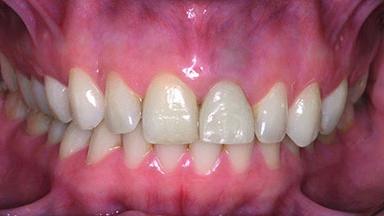

Replacement of a Perforated Upper Left Central Incisor: Early Placement of an RC Bone Level Implant

A 28-year-old patient presented at her general dentist’s office and complained about the appearance of her tooth 21. The patient had a history of trauma to this tooth. Endodontic treatment had been performed in the past and a crown placed on the tooth. A procedure to replace the old crown was performed by her dentist; however, a perforation on the middle third of the root occurred, and extraction of tooth 21 was suggested. Upon clinical and radiographic examination of the patient, who had been referred to us, replacement of tooth 21 by a dental implant appeared to be indicated.

Soft Tissue Contour and Volume Ideal